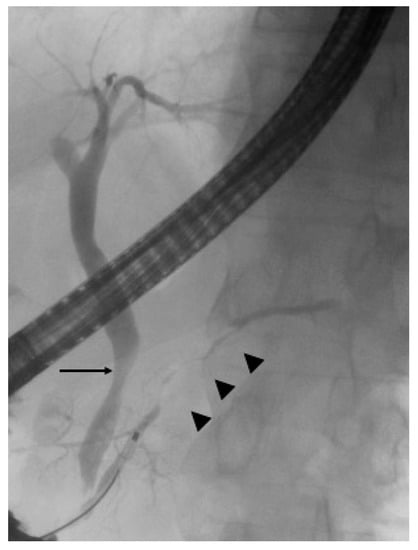

3.1. Endoscopic Retrograde Cholangiopancreatography

3.2. IDUS